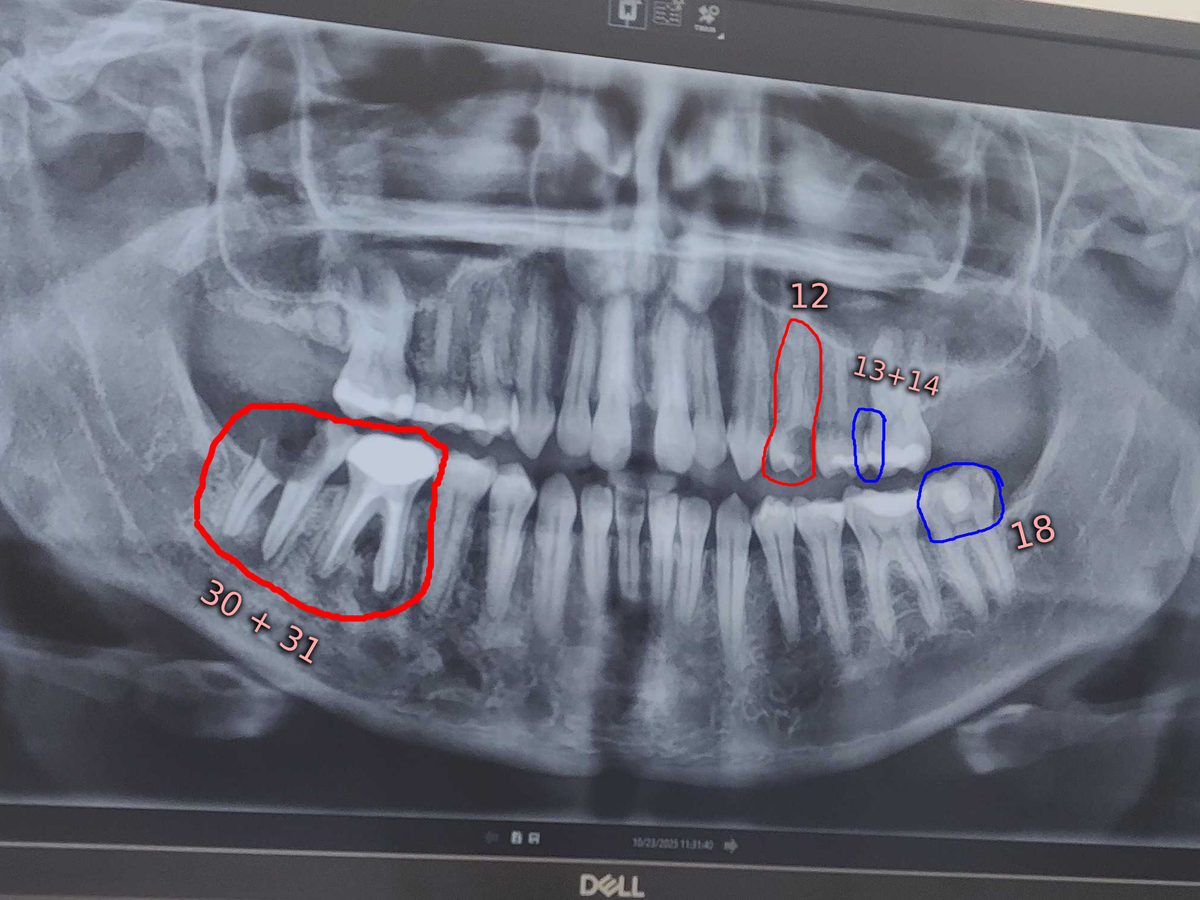

Two weeks ago, part of my back molar broke off. you can see it in the x-ray; the one that's just the roots pretty much. I had a dental appointment this past week where we discovered several pressing issues and decided different treatment options with the original cost for everything being only around $17,200USD.

However, the day after my exam, the majority of one of my front tooth (12) that I had plans to save, broke off.

In my photos, I have included the original bill for each part of the treatment plan. I'm unsure how they'll want to handle the newly ruptured tooth, but they had already suggested extraction before it was ruptured like this. It is likely that it will need to be removed and have a bone graft as well. My changes to the bill total are my own math, based on their prices included for extraction, bone graft, and implants, for the newly ruptured tooth.

Each part of this process will be expensive as you can see. But, each part can be done in different times. At the moment, getting the implants is not a primary concern. They are something I would genuinely like to do, but I want to focus on the core health issues. Which is the removal and bone graft of the teeth circled in red and the fixing of the teeth circled in blue.